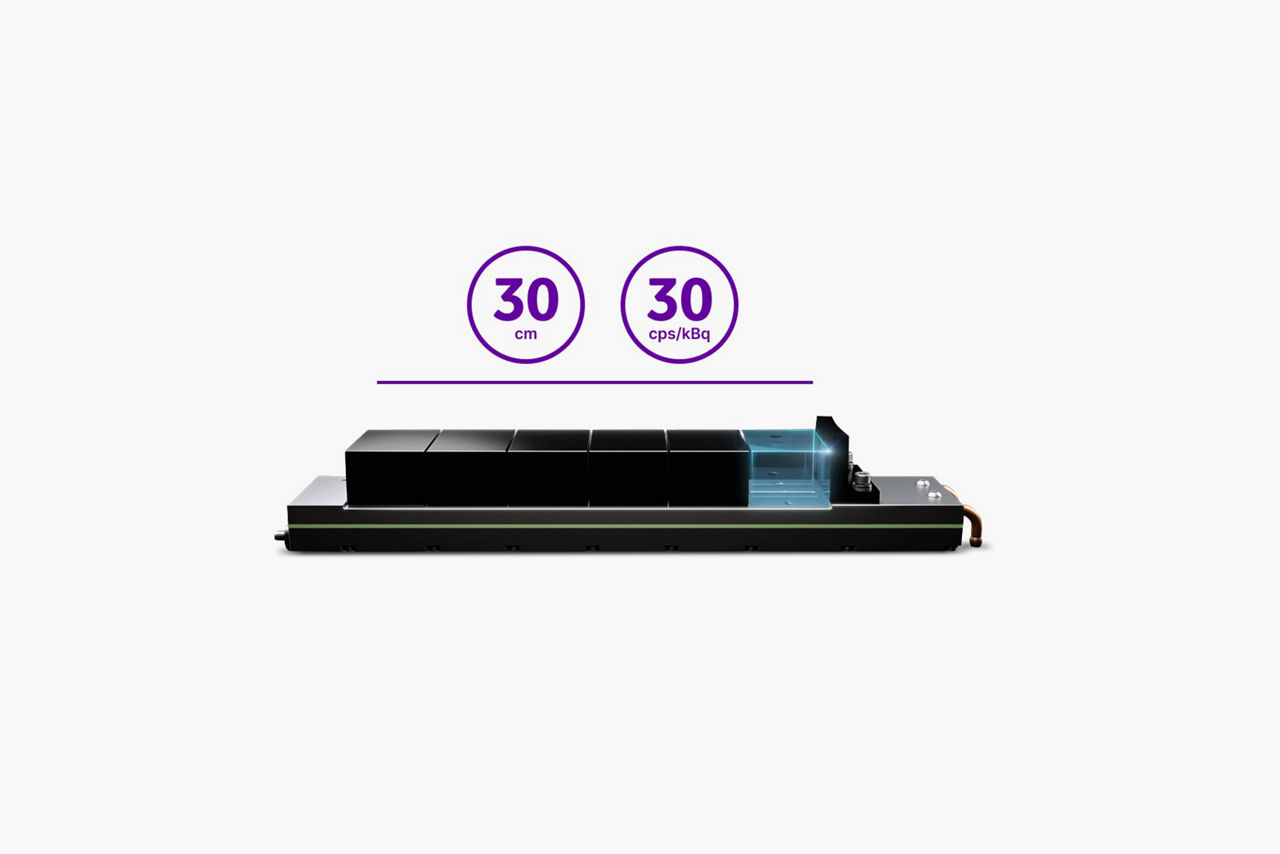

Our goal is to expand your clinical perspective with up to 30 centimeters of coverage, system sensitivity of up to 30 cps/kBq, trusted Q.Clear quantitation, and the proven clarity of MotionFree images. The promise of the digital PET experience is stronger than ever with next generation digital PET technology and an efficient technologist experience provided by Discovery MI Gen 2.

In PET imaging, sensitivity is everything. It affects your ability to detect small lesions, your scan length and dose amounts. Each row of the Discovery MI Gen 2 LightBurst Digital Detector adds five centimeters to your total field of view. Discovery MI Gen 2 can expand all the way up to 30 centimeters of coverage, providing a 50 percent increase in peak NECR3, as well as exceptional system sensitivity that reaches 30 cps/kBq.